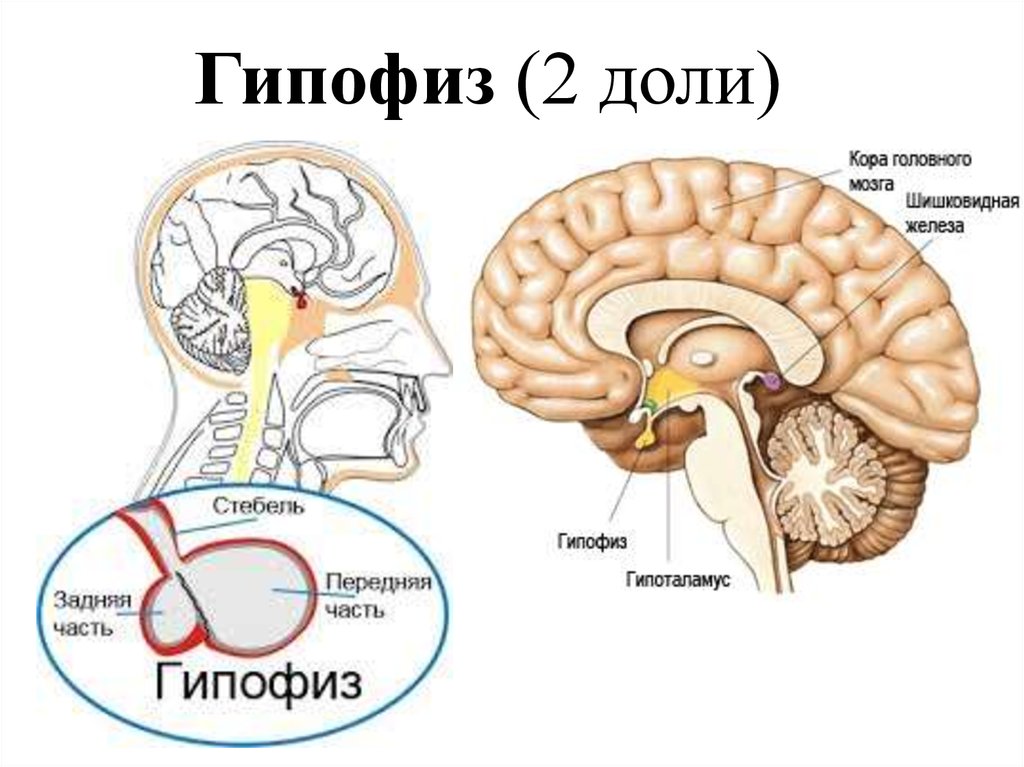

Как работает центр насыщения в гипоталамусе: визуальные иллюстрации